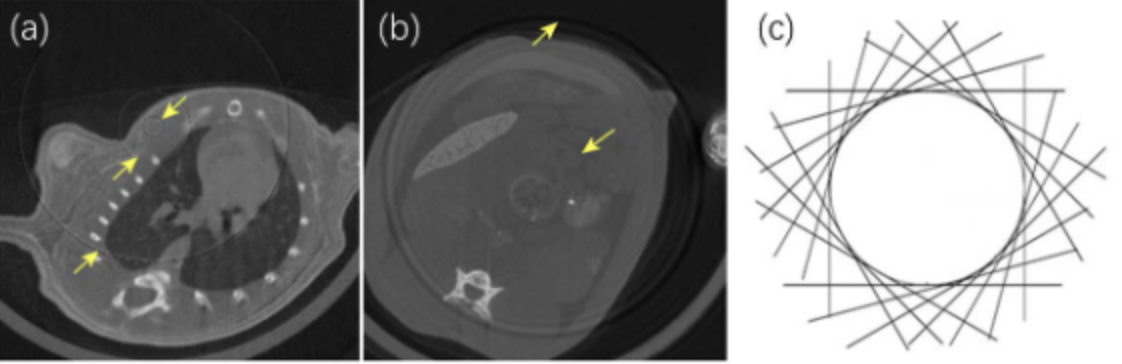

环状伪影是最常见的一种伪影,通常表现为以旋转轴为中心的圆或者弧。显微 CT 所使用的探测器会有一定几率出现像元通道的缺陷或对射线的非线性强度响应,从而导致探测器中某些像元对射线响应不一致。在成像时,探测器上单个像元对应一条光线的数据,由于射线源和探测器始终绕旋转轴做圆周运动,因此响应不一致的像元绕旋转轴旋转一周后,异常投影数据的叠加就形成了圆环,在重建图像中就会形成环状伪影。若探测器上出现连续异常像元,那么环状伪影就会存在一定的宽度,这类环状伪影在重建图像中会表现得异常明显【1】。

(a)(b)环状伪影示意图;(c)环状伪影的成因。图片来源于文献【1】